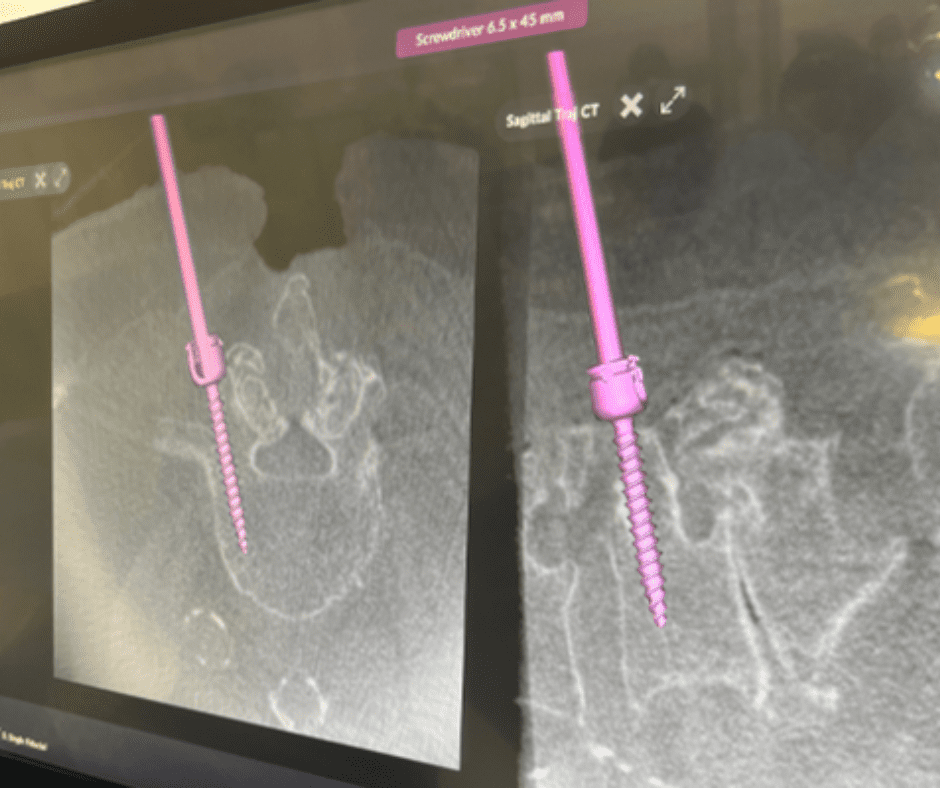

The NuVasive Pulse system brings together a range of operating theatre technologies to support neurosurgeons in reaching a new level of precision and accuracy. In a single platform, Pulse enables technologies such as neuromonitoring, surgical planning, rod bending as well as imaging and navigation functions.

The NuVasive Pulse is the first, single platform to integrate multiple technologies to assist neurosurgeons adopt more efficient, less disruptive surgical approaches in spine procedures. The system has been engineered to improve workflow, reduce variability and increase surgical reproducibility, assisting our neurosurgery team address a broader range of clinical challenges that may present in the operating room.